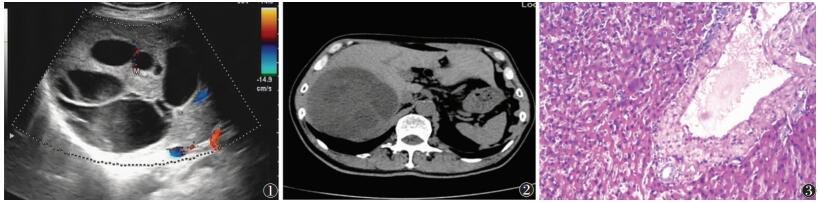

男,69岁,腹胀15 d余入院。查体:腹部平坦,未见胃肠型及蠕动波,无腹壁静脉曲张。腹肌软,无压痛,无反跳痛,Murphy征阴性,未触及肝、脾、肾及其他肿块。实验室检查:AFP < 1.80 ng/mL。影像学检查:①超声示肝右后叶探及一囊实混合回声结构,大小12.6 cm×12.6 cm×10.7 cm,边界尚清,形态尚规整;CDFI示其内及周边未见明显血流信号。超声示肝右叶囊实混合性结构,性质待查(1.复杂性囊肿,2.其他?),建议进一步检查(图 1)。②CT示肝脏右叶巨大囊实性肿块,大小10.6 cm×11.3 cm×11.2 cm,增强扫描实性成分及分隔强化。CT诊断:肝右叶囊实性肿块,恶性不除外(图 2)。手术及病理:行右半肝切除术,术后送检标本为囊实性肿块,病理结果:考虑肝脏间叶性错构瘤(mesenehymal hamartoma of the liver,MHL)(图 3)。

图 1 肝右后叶探及一囊实混合回声结构,边界尚清,形态尚规整,CDFI示其内及周边未见明显血流信号  图 2  CT示肝脏右叶巨大囊实性肿块,增强扫描实性成分及分隔强化  图 3  病理:以肝细胞为主要成分,含有胆管、血管,有丰富结缔组织增生(银染×40)